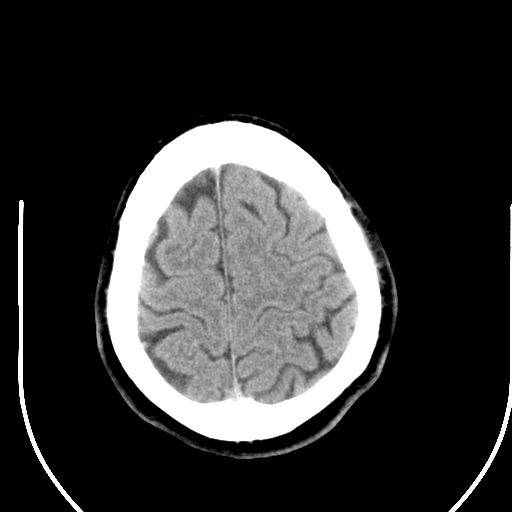

标题: CT25423:头部外伤意外发现右顶叶??? [打印本页]

标题: CT25423:头部外伤意外发现右顶叶???

ct值约13hu。

边缘清晰,没有占位效应,不像脑沟,结合ct值,软化灶可能吧

与脑沟没关系,小软化灶或陈旧性感染吧!

看样年纪不小了直接报腔梗,当然你要想报软化灶也是一样的

考虑右侧额叶巨腔隙灶;建议必要时行mri检查。